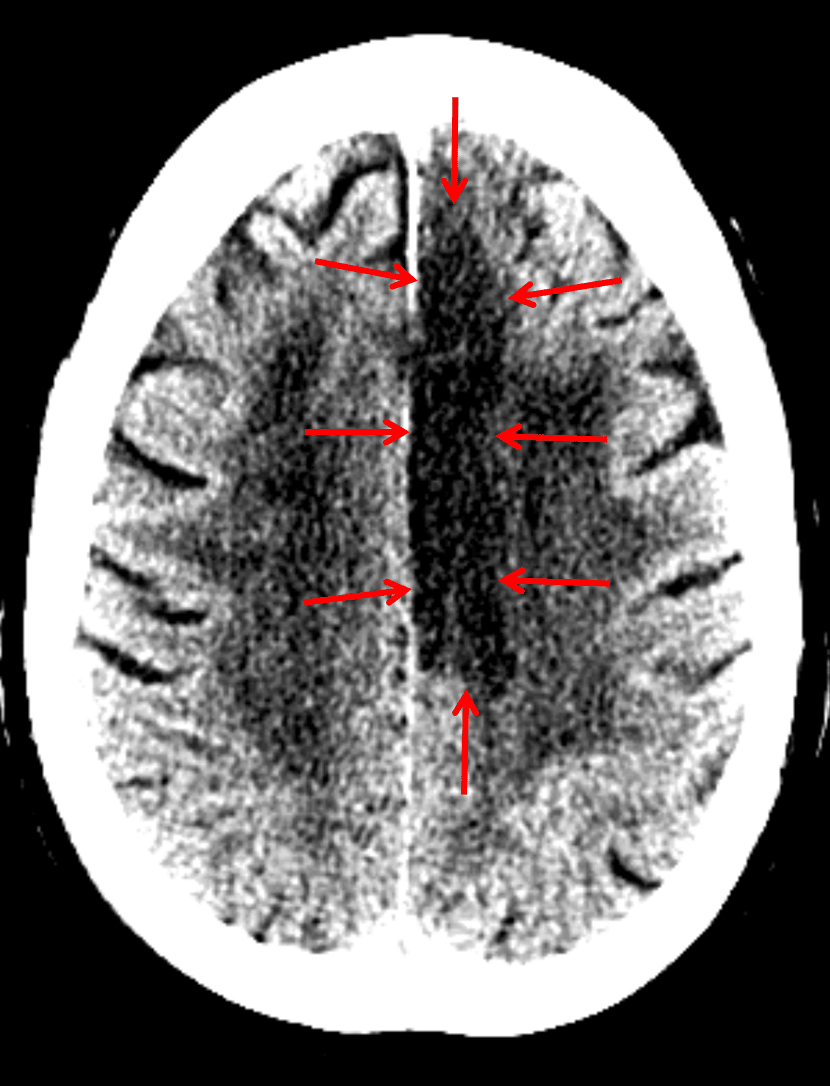

Findings

- Hypoattenuation and loss of gray-white differentiation involving the left paramedian frontal and parietal lobes

- Remote left basal ganglia lacunar infarct

- Sequelae of chronic small vessel disease

Diagnosis

Left ACA territory infarct

Sample Report

Hypoattenuation and loss of gray-white differentiation involving the left paramedian frontal and parietal lobes consistent with acute/early subacute left ACA territory infarct. No significant associated mass effect or evidence of hemorrhagic conversion.

Remote left basal ganglia lacunar infarct.

Sequelae of chronic small vessel disease.

Annotated Images & Illustrations

Red arrows: ACA territory infarct